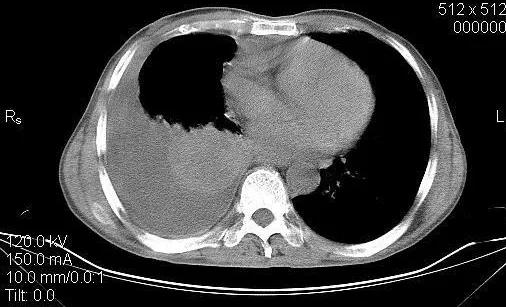

因为输液两天了体温仍高,而且听诊肺部里的胸腔积液更多,这不是个好现象,我开始以为是左氧氟沙星效果不行,所以今天换成了莫西沙星,同时做了个肺部ct, 结果见下图:

而且大哥的白蛋白27g,尿蛋白1+,结合此前有过咯血,最近吃饭不香,人也瘦了许多,这个结果我没敢告诉大哥,悄悄的告诉了他妻子,好在大嫂心态还好,虽然眼睛已经湿了,但还是坚强的听我说,我给的建议是去上级医院呼吸内科进一步确诊并治疗,不能在我这耽搁,毕竟医疗水平有限,大嫂人很好,说今天输完这个液体温一直没高,还和我商量去哪家医院找哪个专家,想听听我的意见,我给她指了两位在我们当地无论医术还是人品都很好的呼吸科大夫,建议明天去他们那里看看,大嫂同意了我的意见。